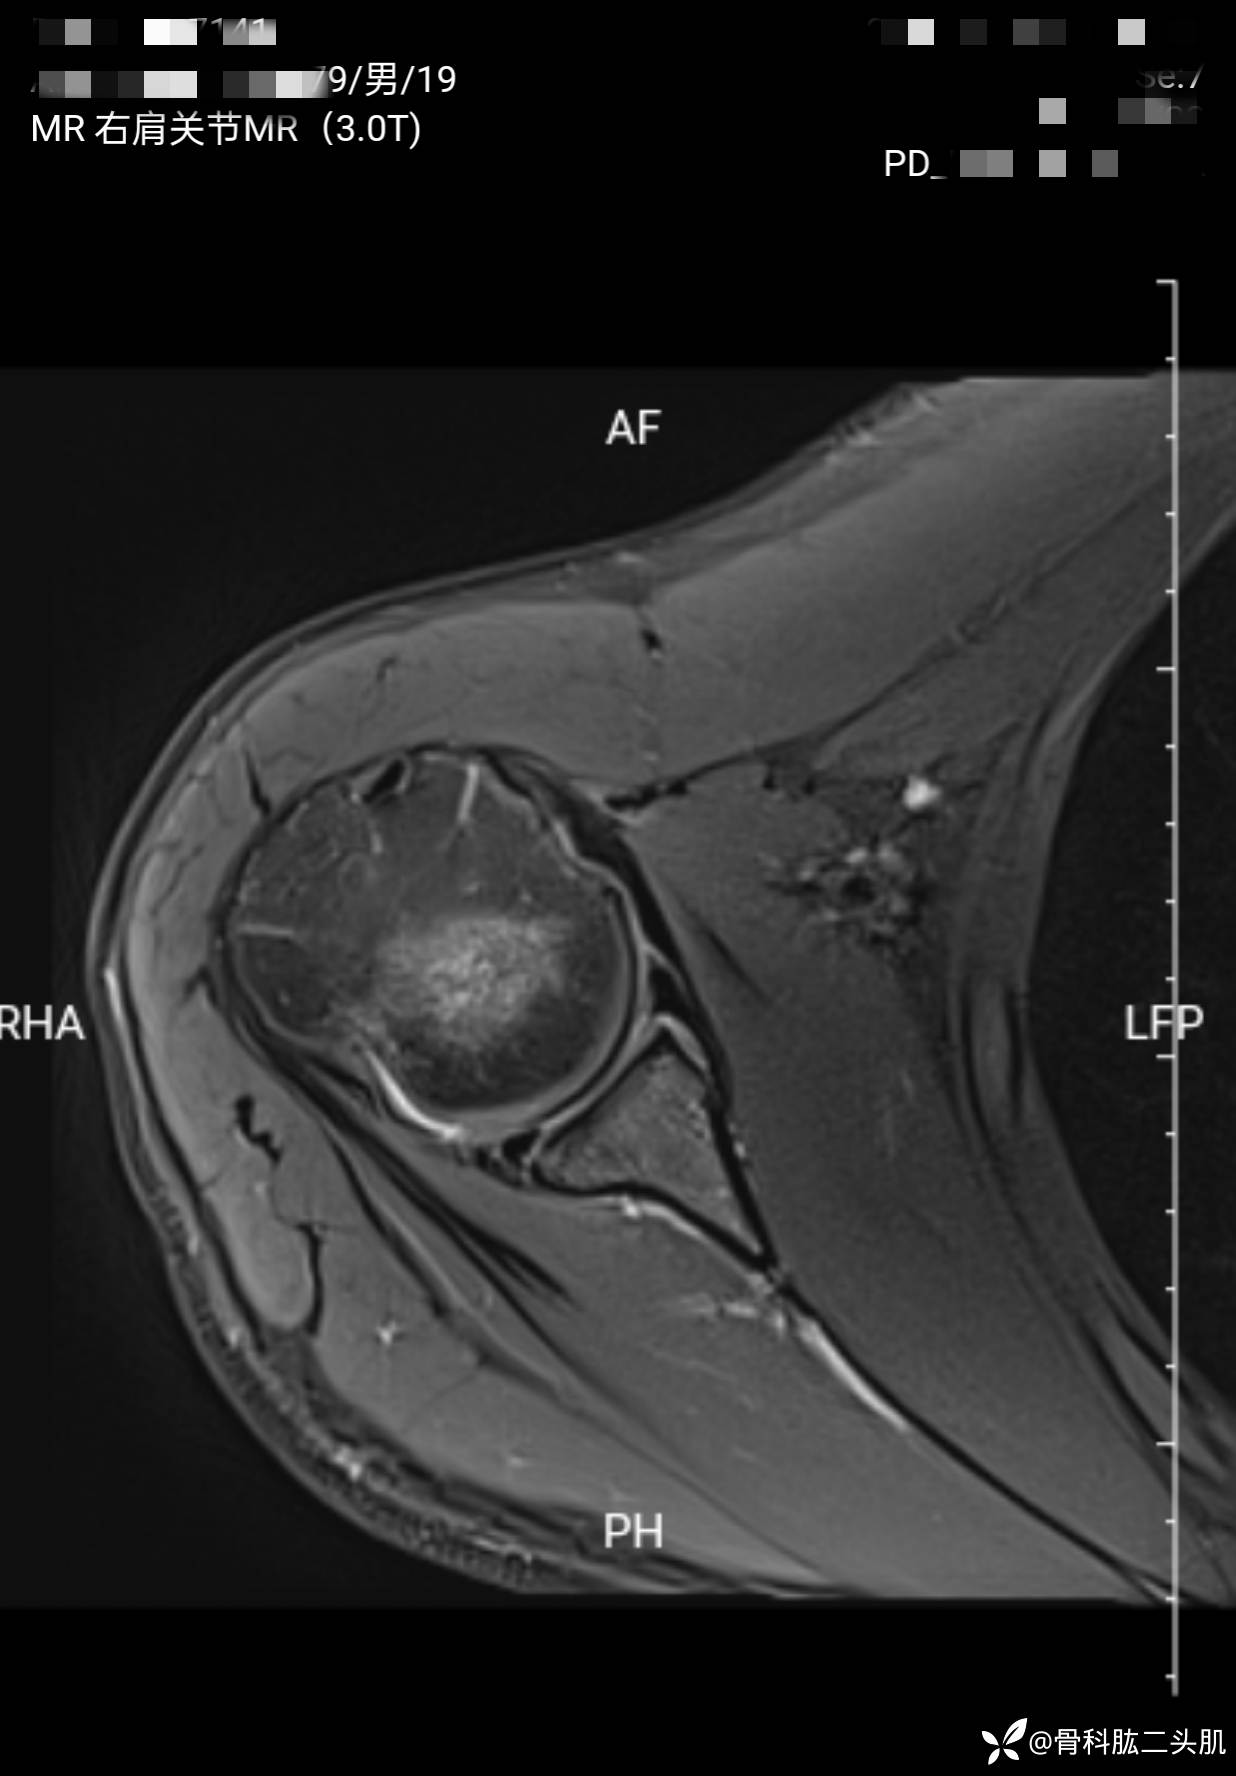

【患者信息】:患者男19岁

【主诉】:右肩关节复发性脱位2年

【检查】:外院核磁示 :右肩前盂唇及上盂唇损伤可能;右肩肱骨头后上缘骨质凹陷;右肩冈上肌肌腱损伤。

【临床诊断】:1.右肩关节复发性脱位 2 .右肩盂唇bankart损伤 3.右侧肱骨Hill—sachs损伤